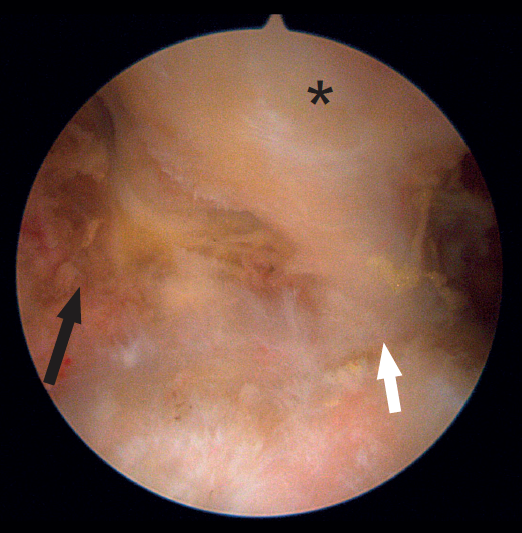

Figure 2. Endoscopic view of the tendon of origin of the left rectus femoris. The optics are located anterior to the joint capsule of the hip (which occupies the floor of the image). Note the direct tendon (black arrow) originating in the anterior inferior iliac spine, the reflected tendon (white arrow) originating in the supra-acetabular region, and the combined tendon formed by the joining of the previous tendons (asterisk).